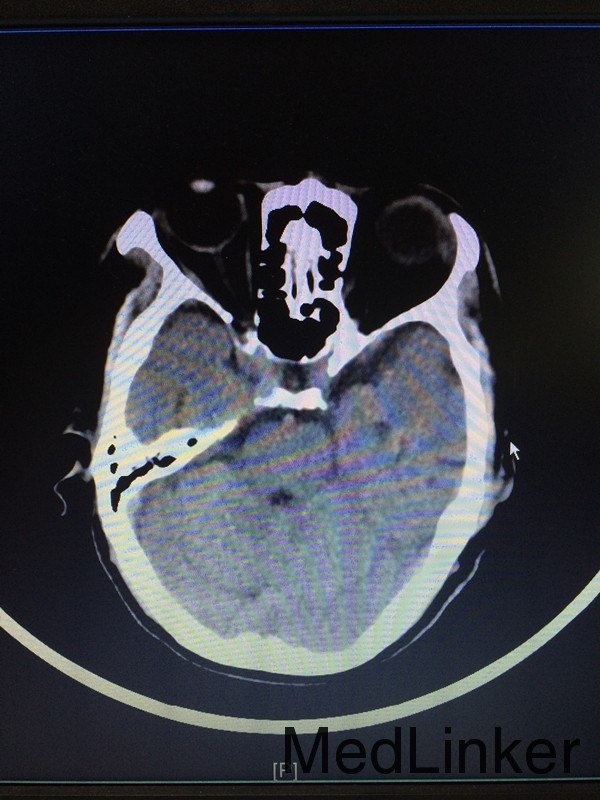

主诉:左侧肢体乏力28天 病史:患者60岁男性,于入院前28天无明显诱因出现左侧肢体乏力,伴言语不清,表现为行走不稳、神志模糊,较烦躁,无头痛、头晕、恶心呕吐等,于当地医院行头颅CT提示:大脑中动脉高密度影。患者第二天出现头痛伴呕吐,急查头颅CT提示:大面积脑梗。

查体:左侧上肢2级,下肢2级,右侧肢体肌力正常 辅助检查:查头颅CTA提示:右侧额叶及岛叶(包括基底节)脑梗塞,轻度脑萎缩,CTA未见明显异常

诊断:右侧额叶及岛叶大面积脑梗塞 治疗:予活血化瘀、改善血管痉挛、脱水降颅压等治疗,并申请康复、高压氧等治疗。

随访:患者病情缓解出院 讨论:患者60岁男性,突发大面积脑梗塞,可能是由脑动脉主干阻塞所致,CT呈现大片状低密度阴影,多为脑叶或跨脑叶分布,脑组织损害范围较大,临床上除表现脑梗塞的一般症状外,还伴有意识障碍及颅内压增高。不排除为体循环的血栓掉落至大脑动脉引起。